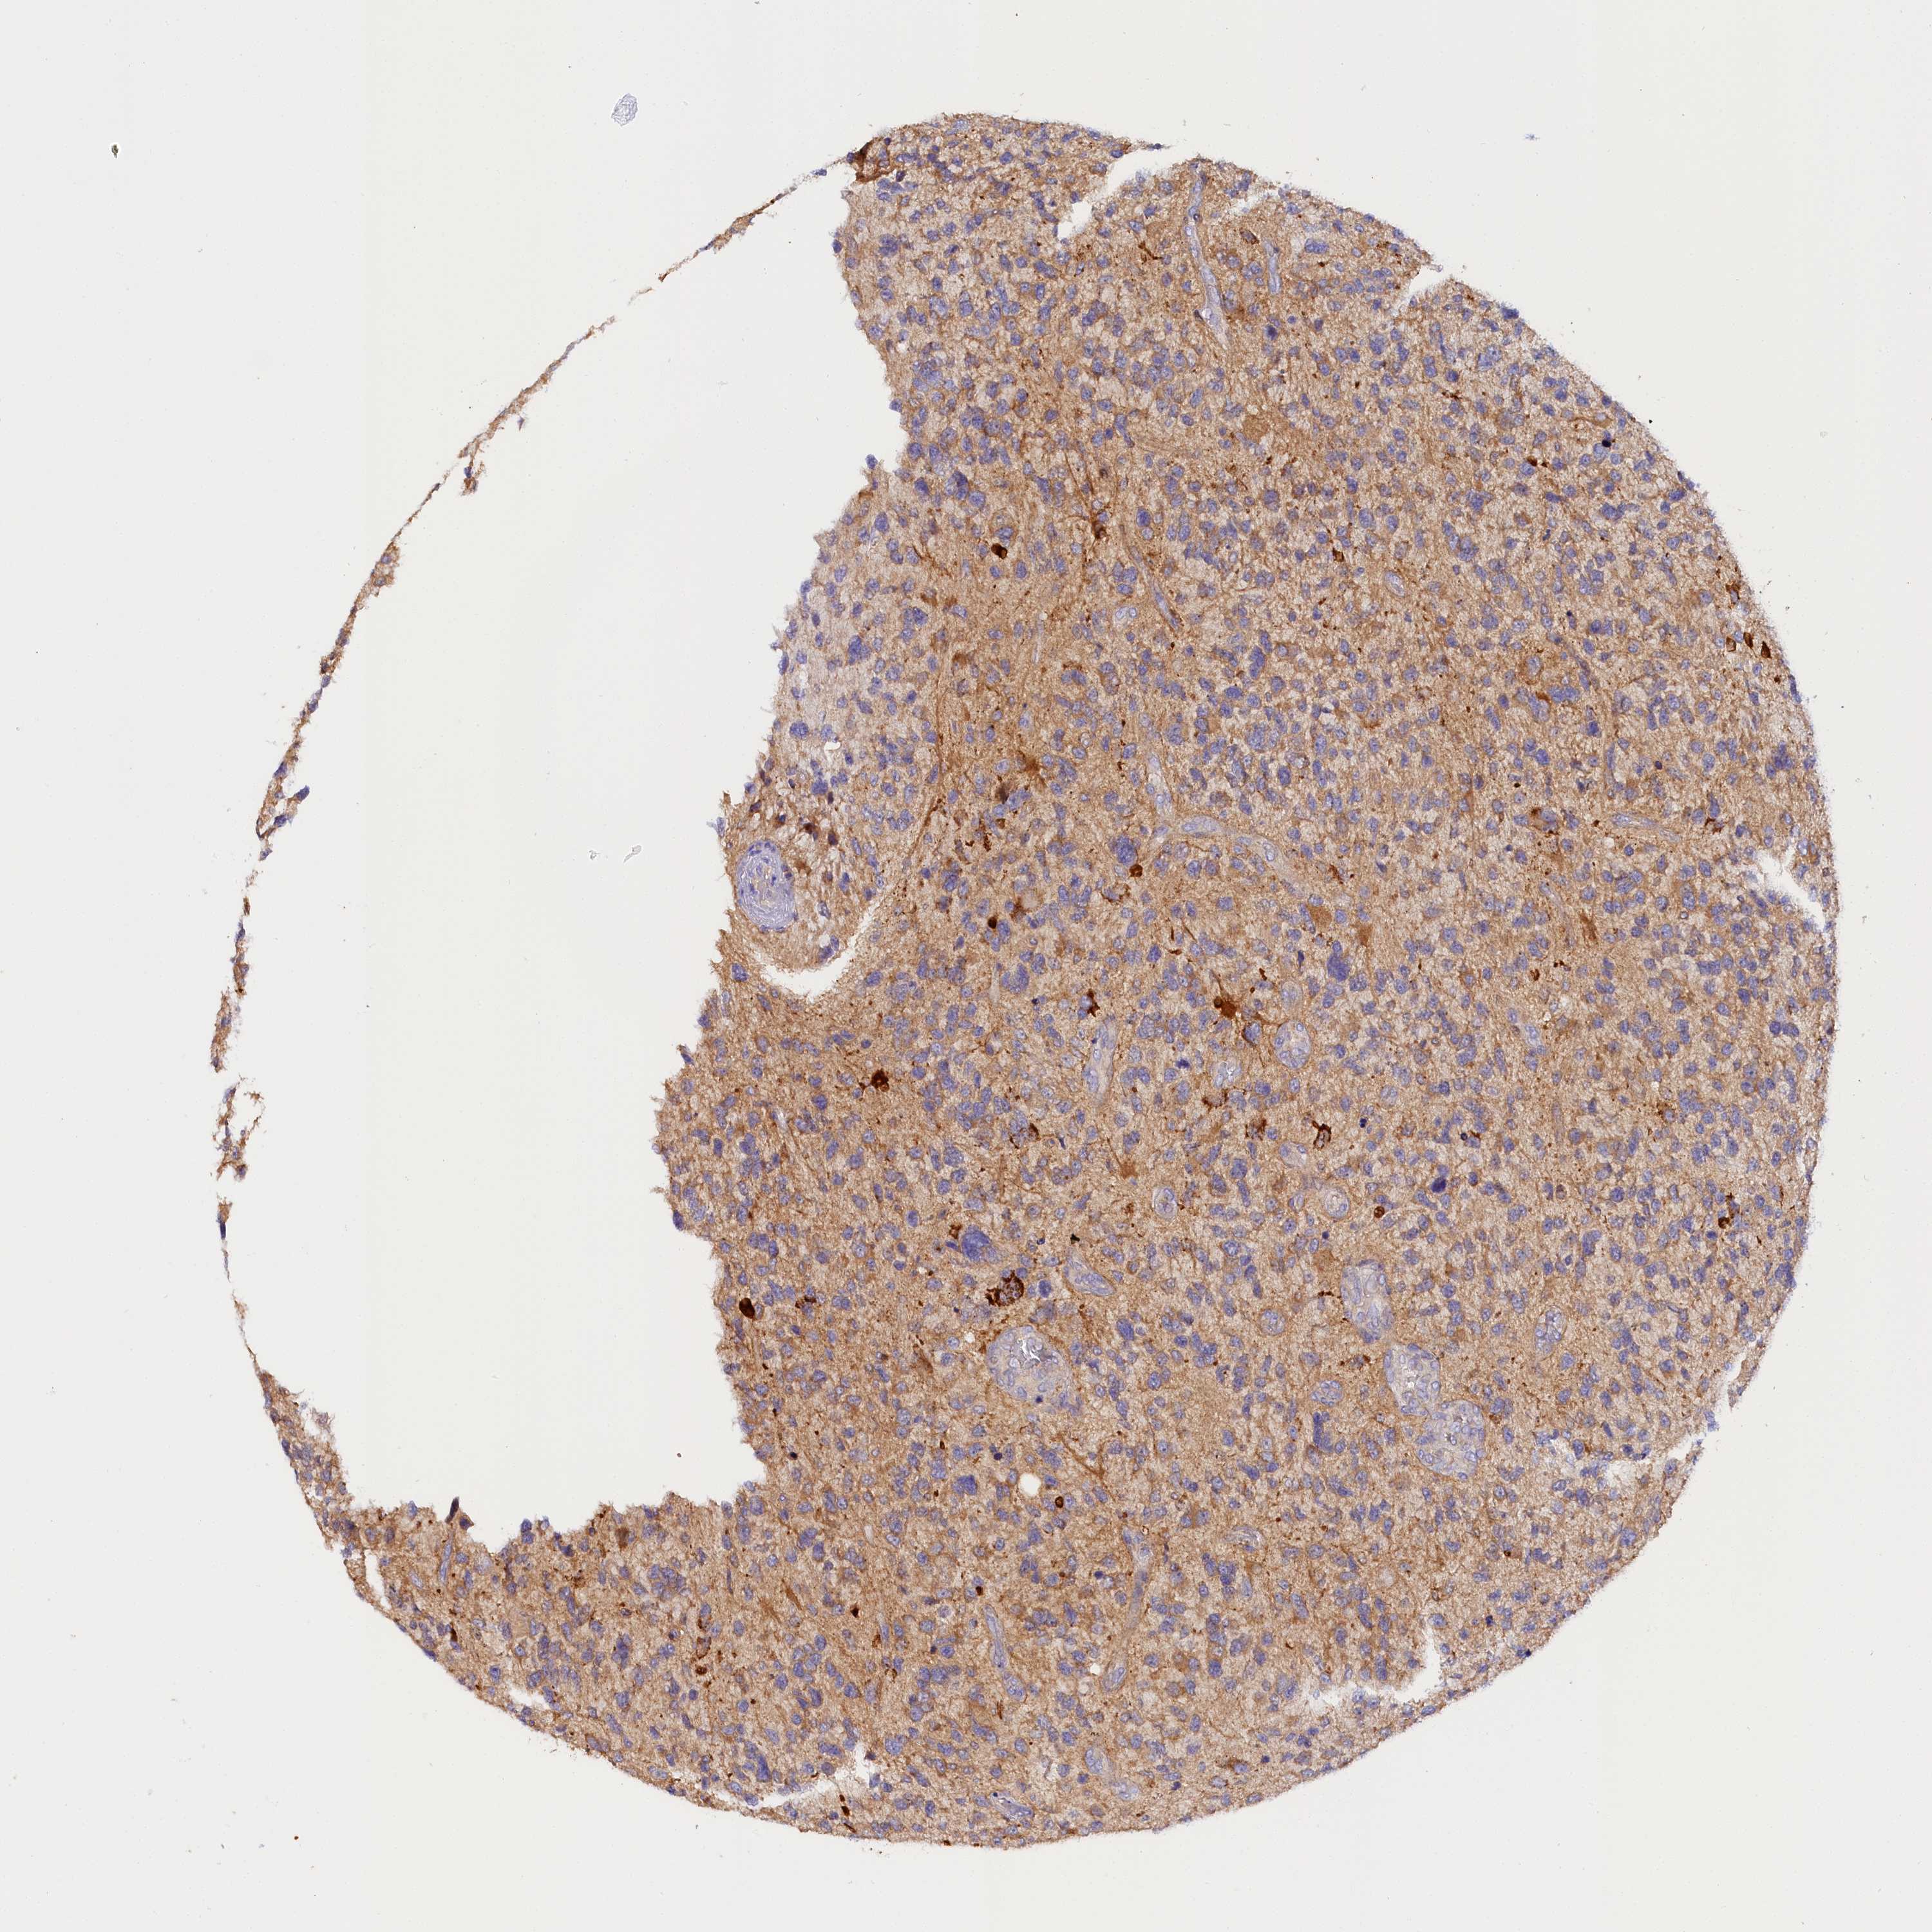

GLIOMA - Protein expressioni

A mouse-over function shows sample information and annotation data. Click on an image to view it in a full screen mode. Samples can be filtered based on level of antibody staining by selecting one or several of the following categories: high, medium, low and not detected. The assay and annotation is described here.

Note that samples used for immunohistochemistry by the Human Protein Atlas do not correspond to samples in the TCGA dataset.

Antibody stainingi

Antibody staining in the annotated cell types in the current human tissue is reported as not detected, low, medium, or high, based on conventional immunohistochemistry profiling in selected tissues. This score is based on the combination of the staining intensity and fraction of stained cells.

Each image is clickable and will lead to virtual microscopy that enables deeper exploration of all samples and also displays staining intensity scores, fraction scores and subcellular localization as well as patient and tissue information for each sample.

Antibody HPA041165

Antibody HPA041839

Staining

High

Medium

Low

Not detected

Intensity

Strong

Moderate

Weak

Negative

Quantity

>75%

75%-25%

<25%

None

Location

Nuclear

Cytoplasmic/membranous

Cytoplasmic/membranous,nuclear

Glioma, malignant, High grade

Glioma, malignant, Low grade